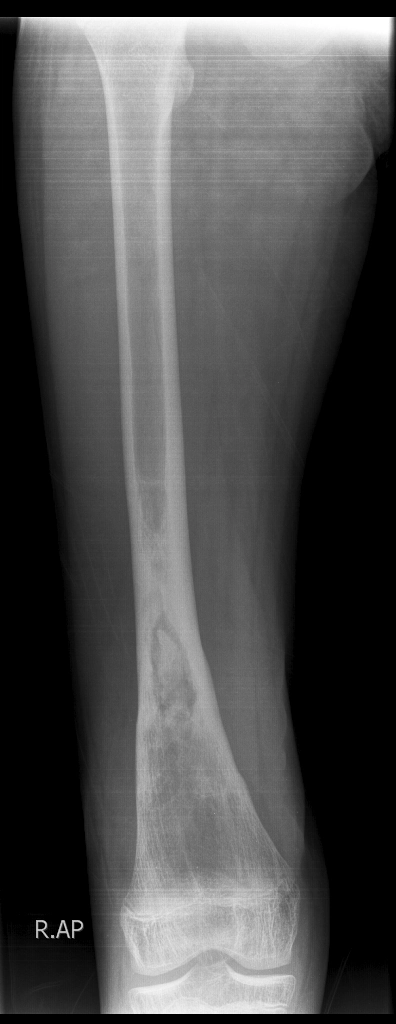

Viêm xương tủy mạn tính (Chronic osteomyelitis)

16/03/2026